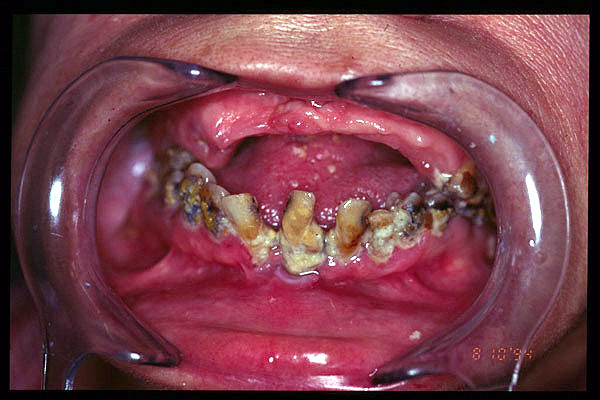

CM Edentulismo parcial, restos radiculares, caries y placa bacteriana